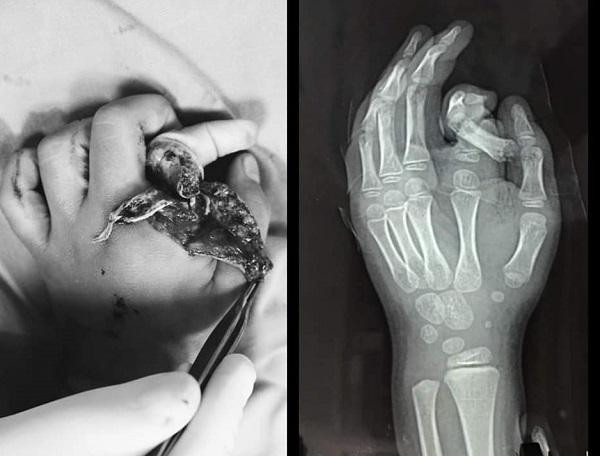

| Hình ảnh ngón tay của cháu bé bị cụt khi nhập viện |

Thời điểm nhập viện, ngón tay trỏ của bàn tay trái bệnh nhi bị đứt rời, tuột da, xoắn vặn, hệ thống thần kinh dây chằng bị nhổ bật một đoạn dài.

ThS.BS Nguyễn Minh Nghĩa, Khoa Phẫu thuật tạo hình và thẩm mỹ Bệnh viện Xanh Pôn – người trực tiếp phẫu thuật cho bệnh nhi cho biết, kíp bác sĩ đã tạo mỏm cụt, khâu bảo tồn cho bệnh nhi.

Tiếp đó, các bác sĩ đã cố gắng để bảo tồn và nối ngón tay của cháu bé, nhưng do tình trạng dập nát quá nặng và bệnh nhi nhỏ tuổi nên không thể nối được.